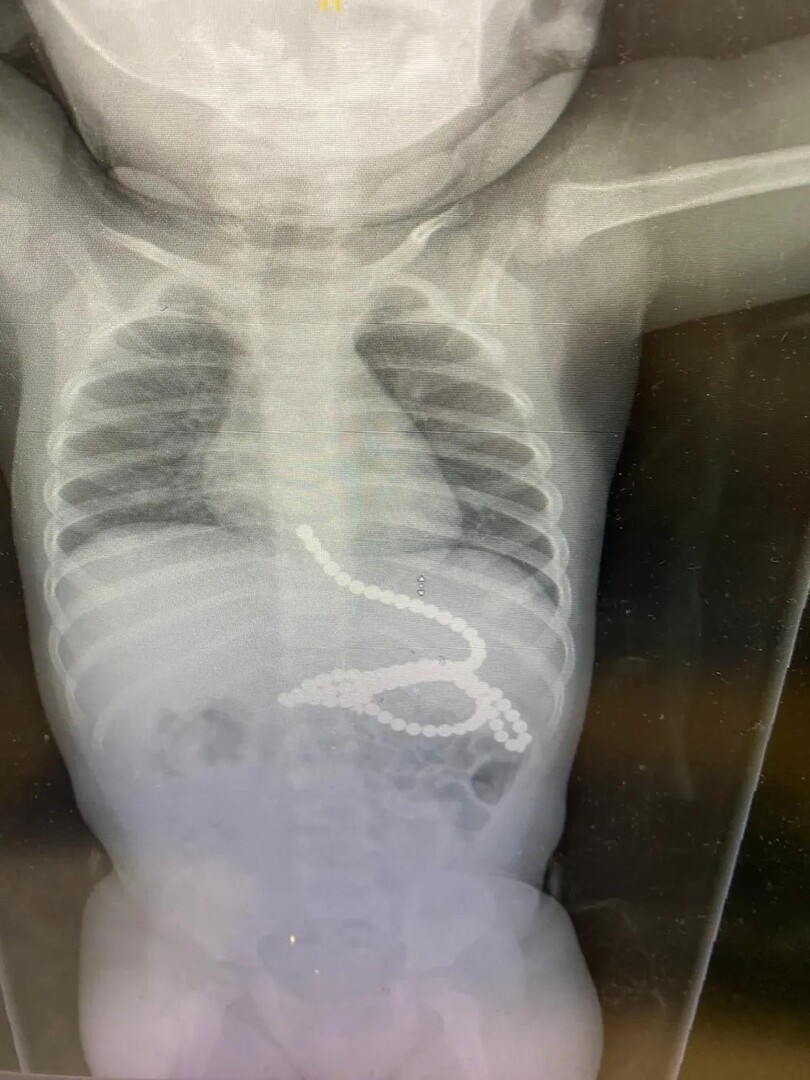

مدار الساعة في حادثة غريبة من نوعها، ابتلع طفل في إسرائيل يبلغ من العمر سنة ونصف السنة، 50 مغناطيسا، واضطر إلى الخضوع لعملية جراحية طارئة.

وفي التفاصيل، وصل والدا الطفل إلى المستشفى، رغم أن الطفل لم يكن يعاني من أي أعراض، وذلك بعد اختفاء بعض الكرات المغناطيسية التي كان يلعب بها.

وفي حديث مع قناة "i24NEWS"، قال الطبيب ناداف سلايفر: "جاء الطفل الصغير إلى غرفة الطوارئ وأدركنا وجود مغناطيسات في المعدة وحاولنا إخراجها".

وأضاف: "ما اكتشفناه في مرحلة معينة هو أن بعض المغناطيسات ليست في المعدة، و انتقلنا إلى الخيار الجراحي، وما وجدناه هو أن بعض المغناطيسات ذهبت إلى الأمعاء الغليظة والأمعاء الدقيقة، وبسبب قوة الجذب بينهما، أحدثت ثقوبا في الأمعاء".

وتابع: "المغناطيسات هي التي حولت الأمر إلى تدخل جراحي. فالمغناطيسات، لأنها يلتصق بعضها ببعض، تعرض الأطفال الصغار للخطر".